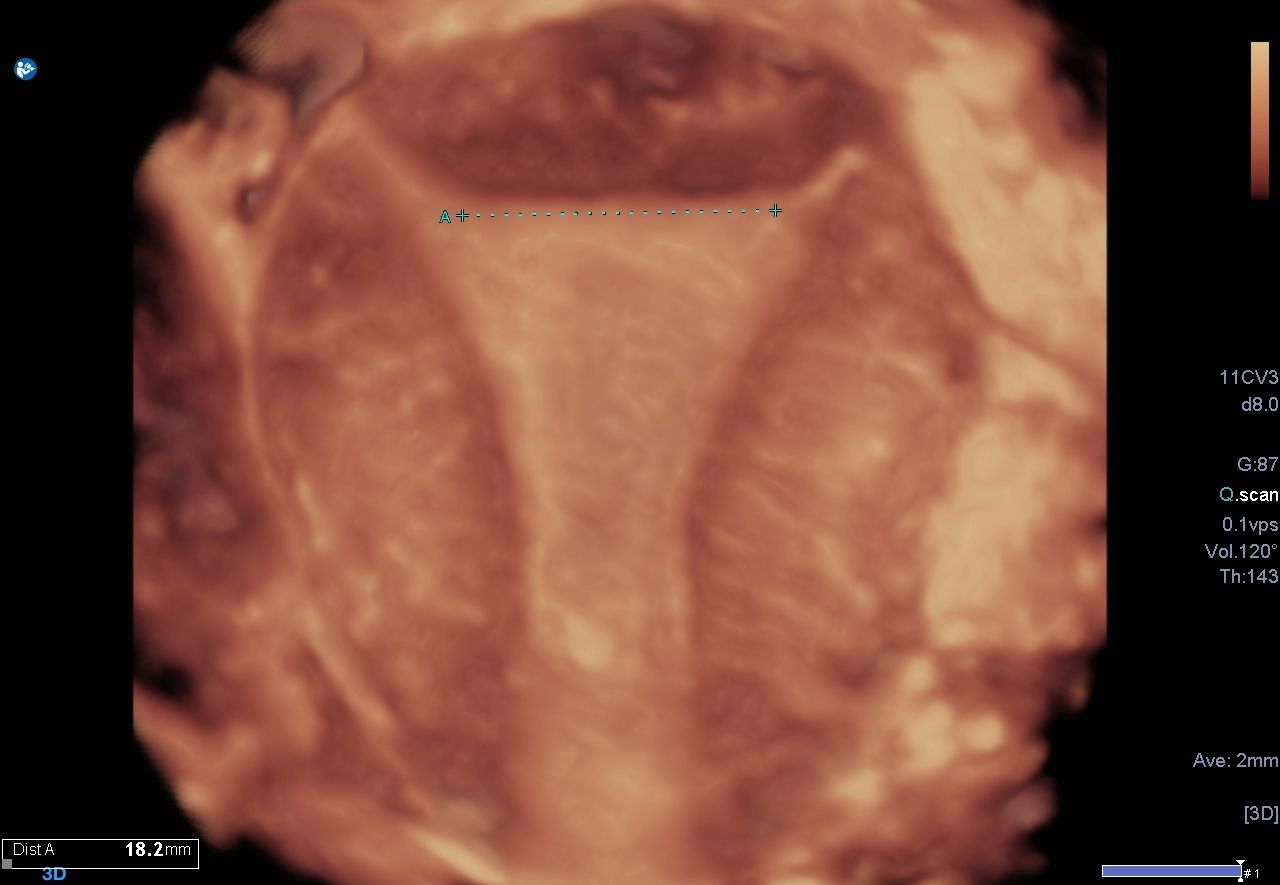

Individuelle Anpassung mit 3D-Ultraschall

Um die passende Spirale für jede Frau zu finden, vermessen wir die Gebärmutter präzise mittels 3D-Ultraschall. So garantieren wir optimale Sicherheit und Komfort.